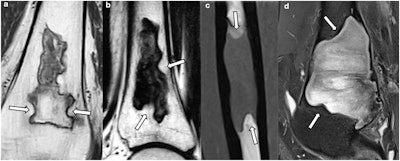

Lesions with at least two concave borders (arrows): a, b osteonecrosis; c, d fibrous dysplasia.Kalaaji et al; Insights Into Imaging

All osteonecrosis lesions, 44.8% of fibrous dysplasia lesions, 20.8% of abscesses, 14.8% of chondroblastomas, 12.5% of Langerhans cell histiocytosis lesions, and 2.9% of metastases showed at least two concave margins. No lesions in the other groups had more than one concave margin.